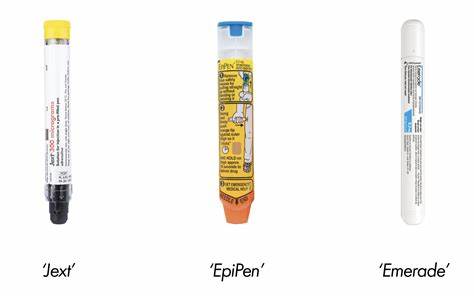

Adrenaline auto-injectors (AAIS) are life-saving devices used to treat anaphylaxis, a severe allergic reaction that can be fatal if not treated immediately. In the UK, common brands include EpiPen, Jext, and Emerade.

The Medicines and Healthcare products Regulatory Agency (MHRA) has issued updated guidance on their safe use. Key recommendations include:

- Check expiry dates regularly and replace expired devices.

- Always carry two AAIs in case a second dose is needed.

- Use immediately if anaphylaxis is suspected—signs include throat swelling, breathing difficulty, dizziness, and confusion.

- Call emergency services (999) immediately after using an AAI.

- Lie down flat and raise your legs to assist blood flow.

The use and management of AAI is best taught in a classroom.